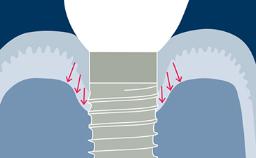

A obtenção de informações detalhadas sobre o histórico médico de um paciente é obrigatória antes que qualquer procedimento cirúrgico como a terapia com implantes possa ser considerado em um plano de tratamento. Atenção especial deve ser dada aos fatores relacionados ao paciente que podem afetar a cicatrização óssea. Esses fatores podem determinar se o paciente é um candidato adequado ao procedimento planejado ou se outras alternativas de tratamento devem ser preferidas. Uma abordagem sistemática para receber as informações pré-operatórias necessárias aumenta a probabilidade de que todas as facetas relevantes sejam elucidadas. Além disso, ajudará o clínico na identificação de fatores de risco potenciais para o tratamento planejado e na revelação de contraindicações relativas e absolutas.